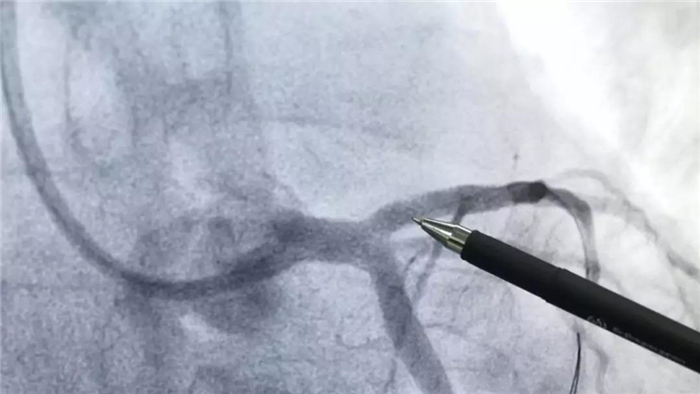

血運(yùn)重建手術(shù)前

在此期間,值班醫(yī)生為患者進(jìn)行了抗血小板、抗凝等治療,并完善了血常規(guī),凝血功能,心肌酶,肌鈣蛋白等檢查。之后,將患者送入導(dǎo)管室進(jìn)行冠狀動(dòng)脈造影檢查,確診了患者為“左冠前降支血管急性閉塞伴血栓”,由于病情兇險(xiǎn)、危急,經(jīng)過家屬同意,邱耀進(jìn)院長(zhǎng)帶領(lǐng)心血管病介入團(tuán)隊(duì),立即進(jìn)行了血運(yùn)重建手術(shù)。

西藏阜康醫(yī)院

血運(yùn)重建手術(shù)后